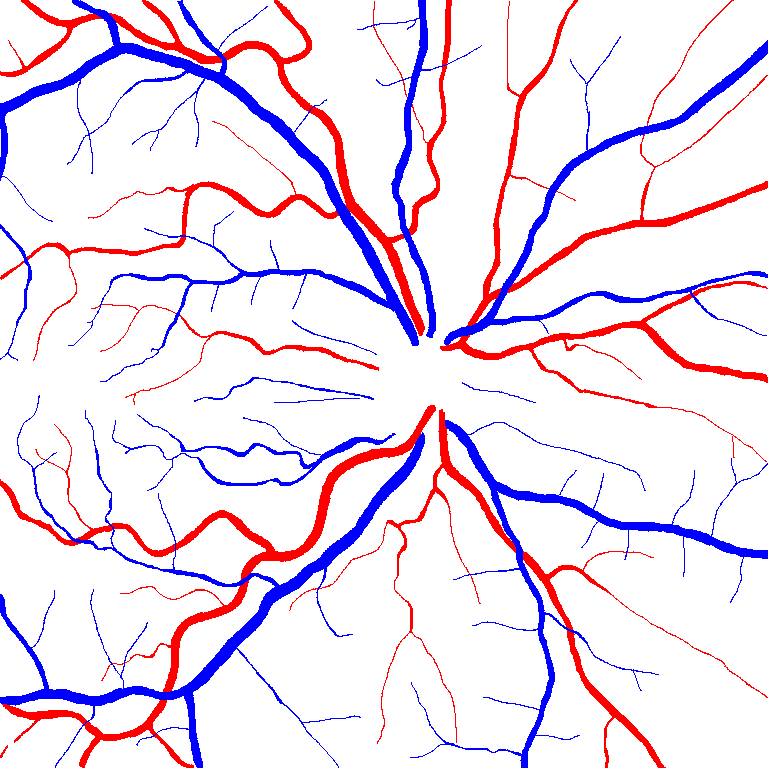

VI-A Retinal Artery and Vein Segmentation

As reported in Table IV, we compared the SegRAVIR model against competing deep learning-based segmentation approaches on the RAVIR dataset. Evidently, SegRAVIR outperforms these methods as judged by all metrics for artery and vein classes with a healthy margin. In terms of Dice score, SegRAVIR outperforms CE-NET, IterNet and AG-Net by , and for artery segmentation and by , and for vein segmentation, respectively. Fig. 4 presents a qualitative comparison of the semantic segmentation outputs of SegRAVIR, CE-Net, and U-Net. Specifically, SegRAVIR yields more accurate vessel topology (i.e., thickness and orientation) segmentation with higher pixel-wise classification accuracy.